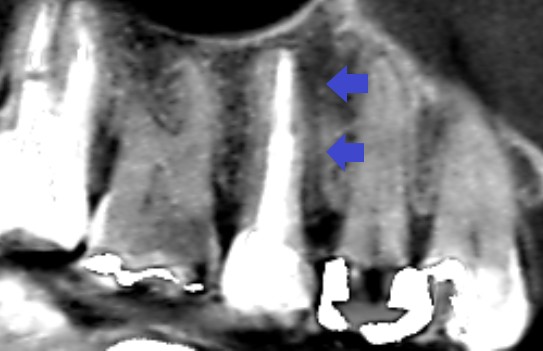

初診時の第二小臼歯のCT画像です。

赤い矢印の先に長い影がみられます。長い影は、歯根破折(ヒビ)の可能性があります。